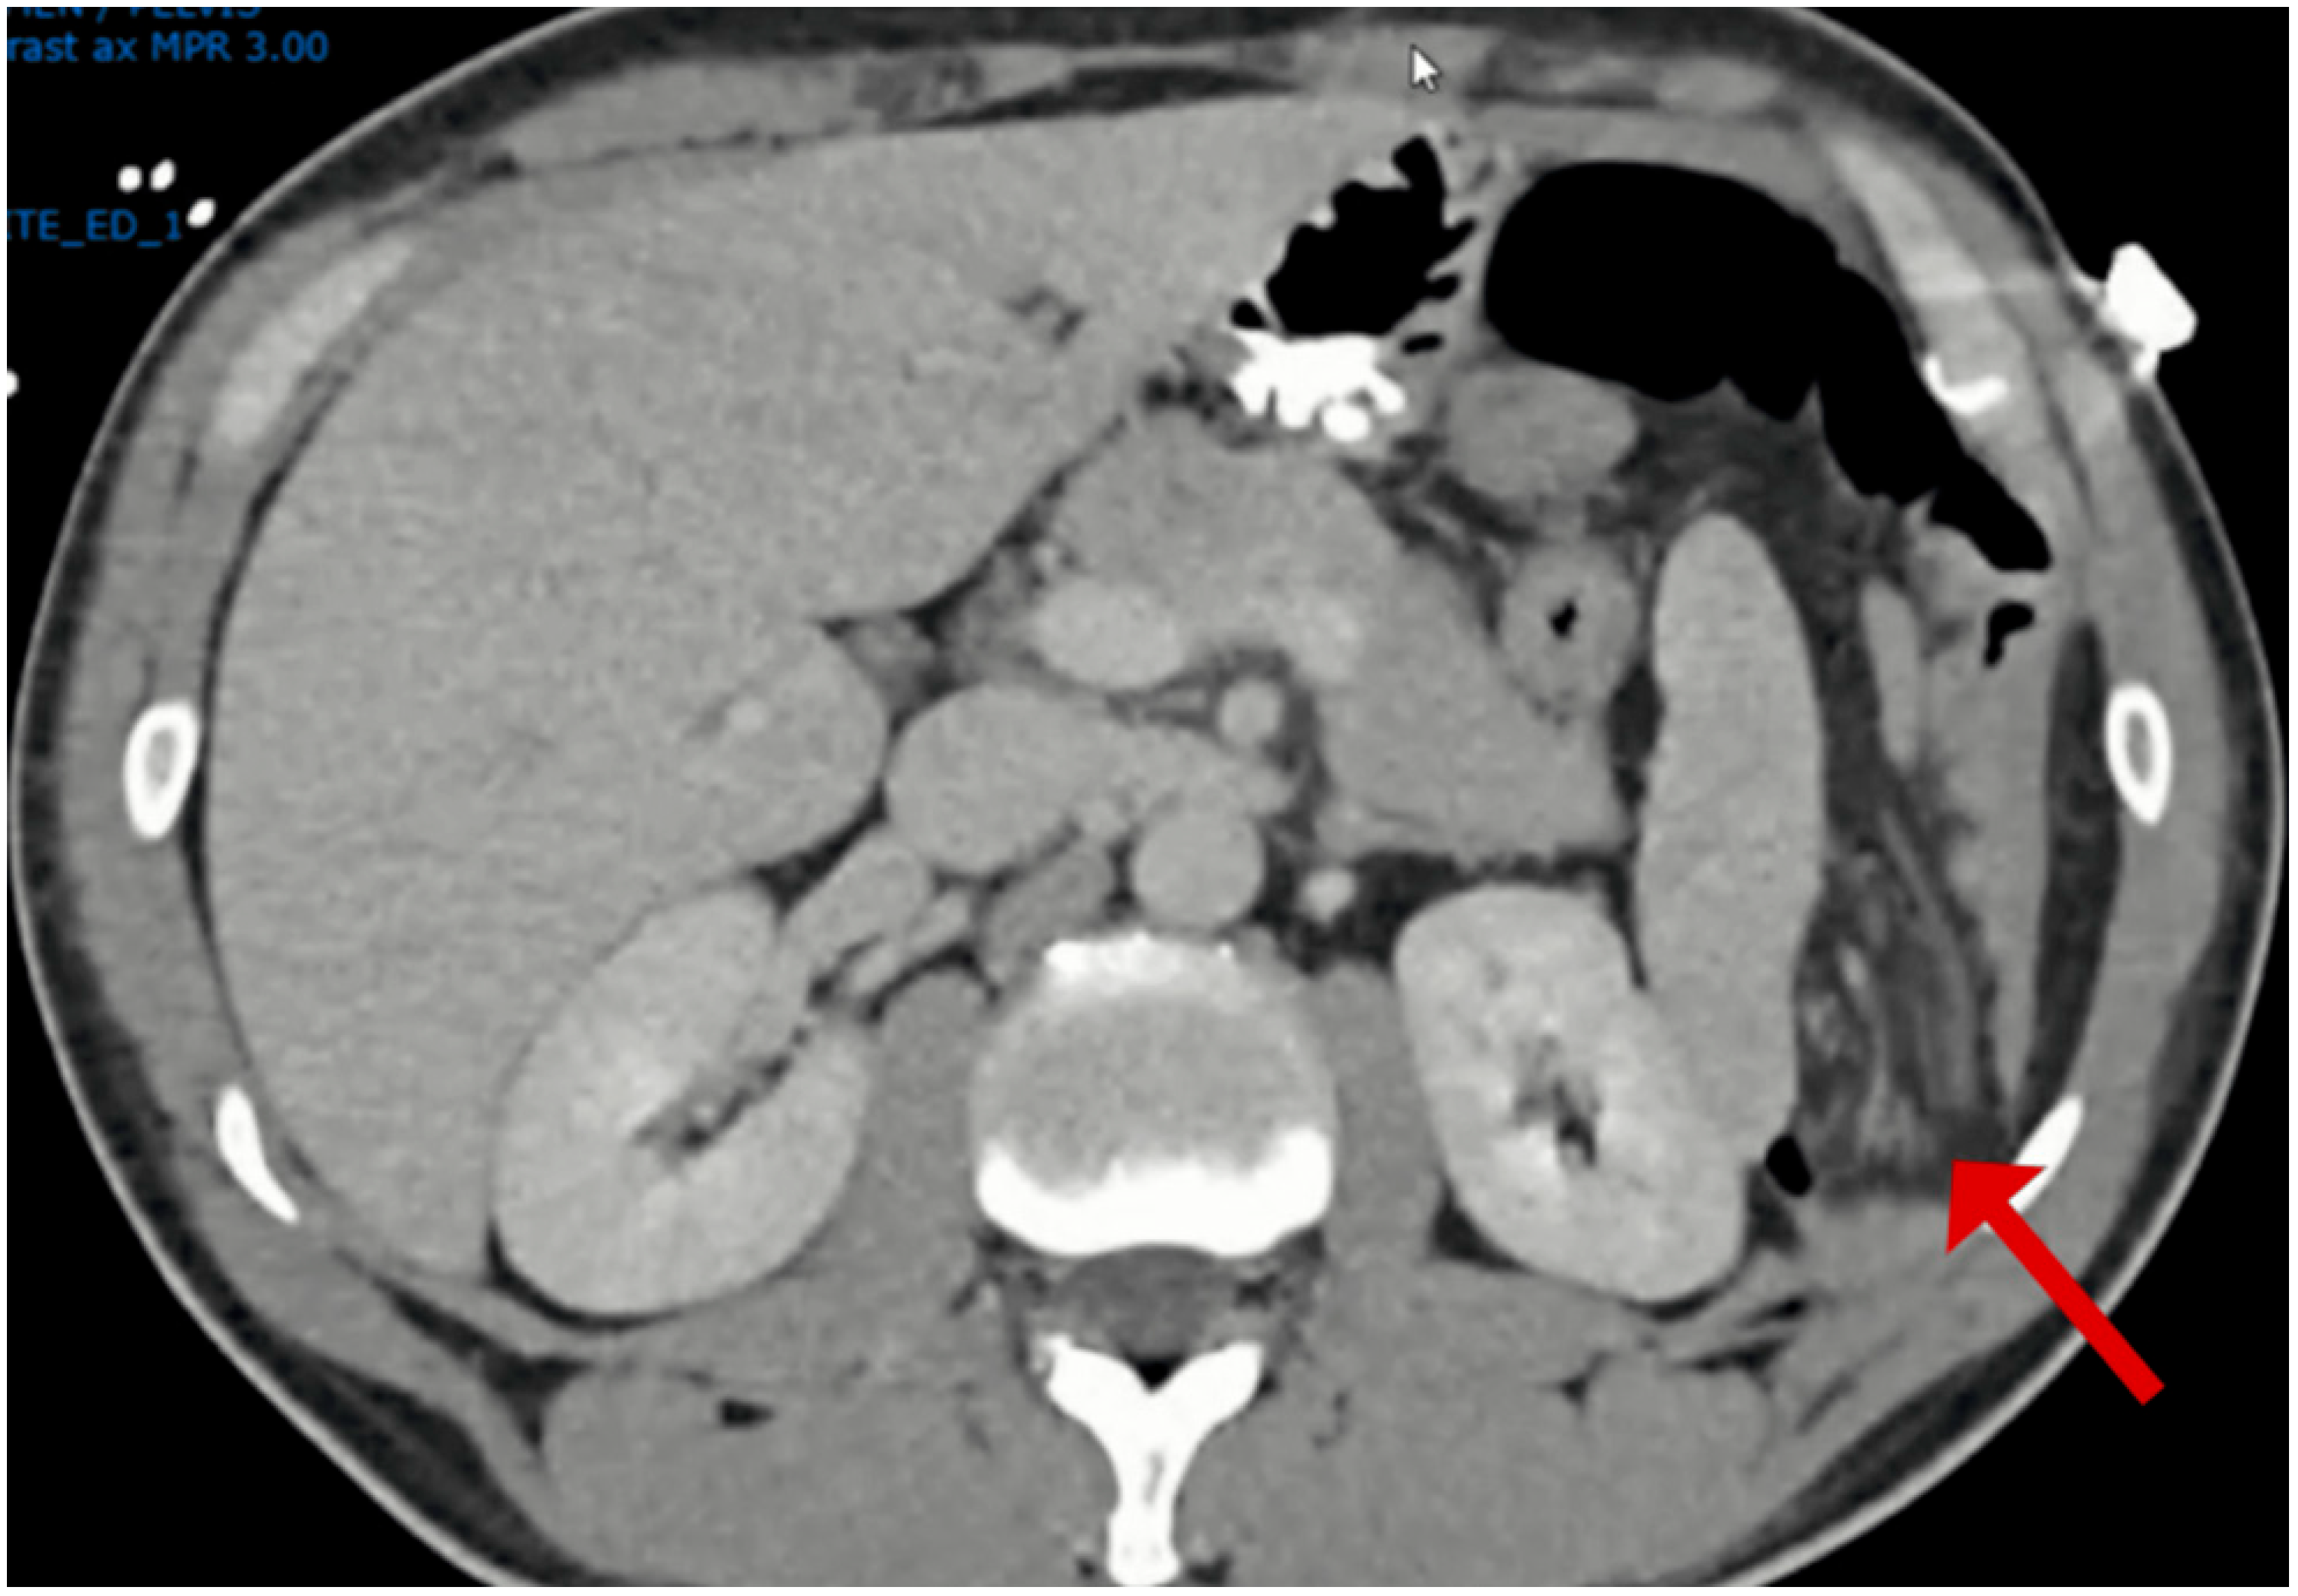

Given the initial suspicion of a perforated peptic ulcer, a non-contrast computed tomography (CT) scan was performed. This revealed a left-sided Bochdalek hernia with small bowel protrusion and signs of strangulation (Figure 1, Figure 2, Figure 3 and Figure 4).

Figure 1. Non-contrast intravenous and oral contrast axial computed tomography image showing defect in Left diaphragm (red arrow) with distended bowel loops.